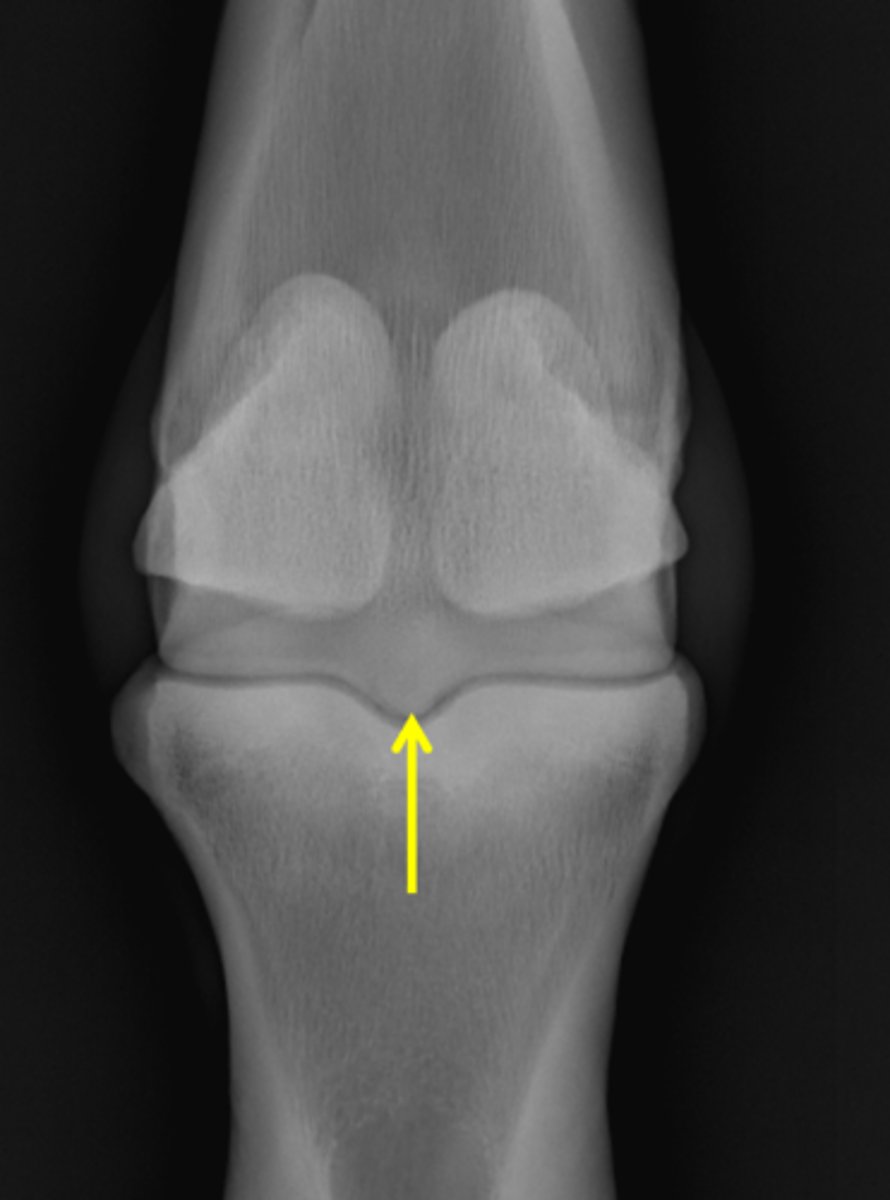

Fetlock joint, DP

ID joint and view

Sagittal ridge

Condyles of third metacarpal bone

Sagittal ridge

Attachment of collateral ligaments

Proximal sesamoid bones

Condyles of the third metacarpal bone